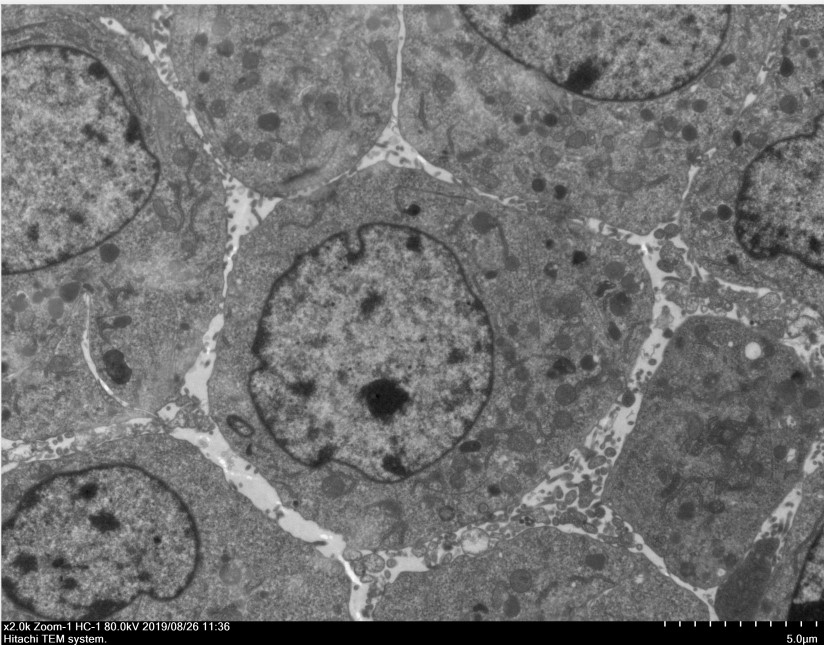

透射電鏡,即透射電子顯微鏡(TEM),電子束在穿過(guò)樣品時(shí),會(huì)和樣品中的原子發(fā)生散射,樣品上某一點(diǎn)同時(shí)穿過(guò)的電子方向是不同,這樣品上的這一點(diǎn)在物鏡1-2倍焦距之間,這些電子通過(guò)過(guò)物鏡放大后重新匯聚,形成該點(diǎn)一個(gè)放大的實(shí)像,可以看到在光學(xué)顯微鏡下無(wú)法看清的小于0.2um的超微結(jié)構(gòu),主要應(yīng)用于物質(zhì)內(nèi)部的超微結(jié)構(gòu)觀察。

四、成果展示